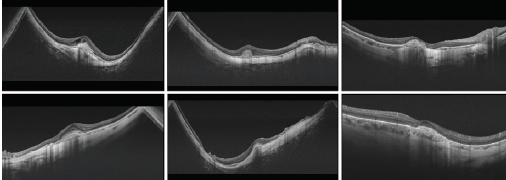

Using SS-OCT, the imaging quality of HM eye has improved. This has enabled us to define new disease states, such as myopic traction maculopathy (MTM) and choroidal cavitations (CC) among others; and has permitted a simpler and clearer study of posterior staphylomas. Myopic staphylomas are defined as evaginations of the posterior wall of the eye with a curvature radius that is smaller than the curvature of the ocular structure surrounding it. This increase in axial length together with tissue thinning is responsible for the appearance of myopic maculopathy (MM) and its different manifestations. Various clinical signs of HM that we include under the name MM include atrophy, CNV, MTM, and dome shape maculopathy.

Using SS-OCT, and especially its 12 mm, single-line scanning mode, we are able to analyze in detail and study curvature modifications that staphylomas induce to the posterior pole of the eye, helping us classify them. This is especially useful in complex staphylomas. Horizontal scans show a progressive and regular augmentation of concavities as the staphyloma increases, from minimal to deep concavities that may even include the optic nerve. In some cases, the optic nerve will stay outside of the concavity, in others it will lay at the bottom of the concavity; in some others a convexity or sinusoidal profile (ascending or descending) can be seen. The majority of vertical scans are concave and regular. Of the more than 700 HM patients that we have studied, vertical scans show concave staphylomas in more than 90% of cases; very few exhibit dome shape morphology.

MTM is a new entity that we are able to study with OCT. We can detect it with SS-OCT and obtain high-quality images. We can separate the internal from external schisis, which can manifest concurrently in the same patient. SS-OCT can also be used to image foveal detachments and to detect and monitor myopic macular holes. It was not possible to do this with so much detail before the advent of SS-OCT.

Dome-shaped maculopathy occurs when there is a dome shape in the macula, along with the presence of fluid between retinal pigmentary epithelium and the neuroretina. It is possible to study this defect thoroughly and with accurate detail using SS-OCT. Swept source imaging also provides vivid details of the sclera making it possible to measure its thickness in our HM patients.

Using SS-OCT, especially large, single-scan protocols (9-12 mm) with horizontal and vertical orientation, we can see and analyze the curvature modifications produced by staphylomas in the posterior pole and the involved structures. This is especially useful in complex staphylomas.